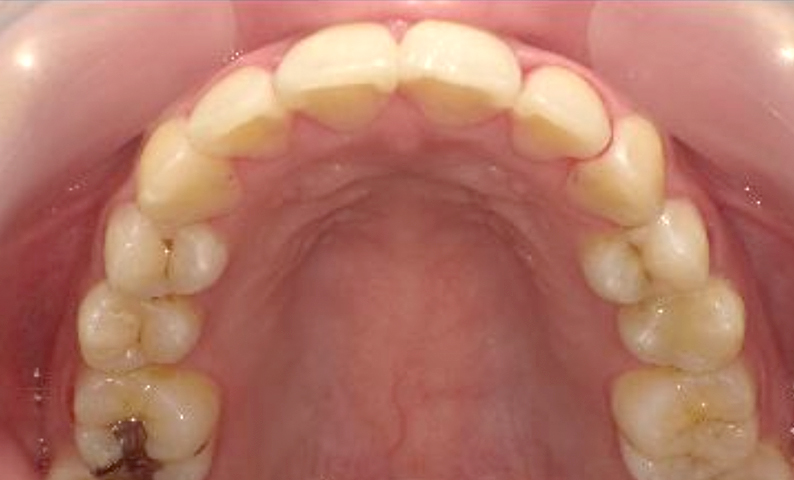

症例_024 上下顎の部分矯正

治療期間:13ヶ月金額:51万円+税女性前歯のガタガタ八重歯

| Before | After |

|---|---|

|